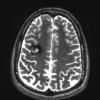

VASCULAR

Cavernous Angioma (9)